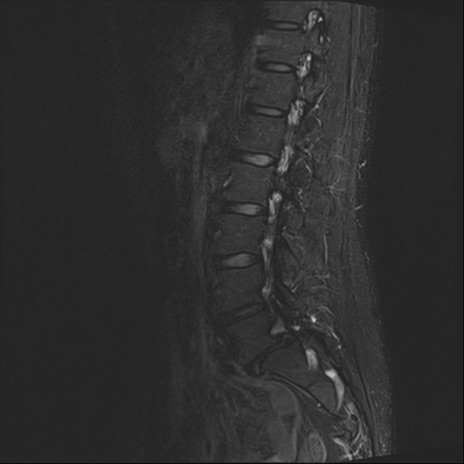

【整形】TIPS症例4 腰椎MRI STIR(矢状断像)

腰椎MRI

T2WI(矢状断像)